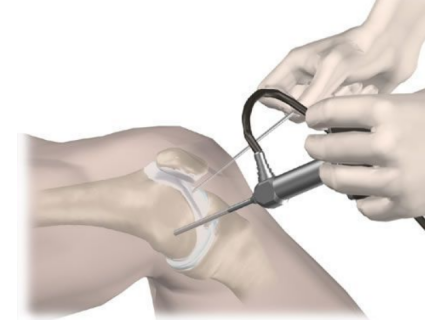

關節鏡在西方被稱為“Key Hole Surgery”,膝關節鏡能對關節內疾病進行檢查、診療,適用于膝關節損傷、非感染性關節炎,膝關節鏡手術被認為是對膝關節病變較好的治療手段。讓我們通過本期文章,揭開膝關節鏡的神秘面紗。

關節鏡構造:

關節鏡基本構造是光學系統、光導纖維和金屬鞘三部分,由關節鏡鏡頭、攝像頭、主機、顯示器和冷光源等組成。將具有照明功能的透鏡金屬管插入關節腔內,在關節內部將圖像在監視器上呈現,在電視監視下進行全面檢查和進行手術。關節鏡可以看到關節內幾乎所有的部位,由于圖像經過放大,醫生可以更準確地把握患者關節內部情況。